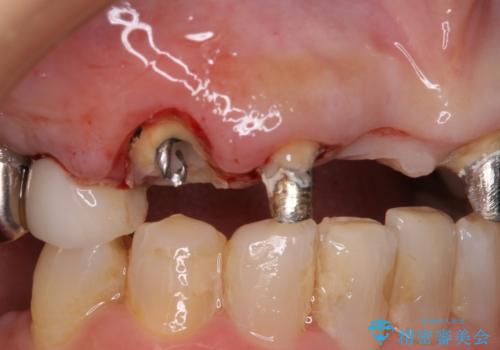

ところが、土台となる歯は、十分な維持力が得られないほど歯ぐきの中に埋もれており、歯ぐきも腫れやすい状況でした。

まずは土台の歯を引っぱり出し、外科処置により歯肉の状態を十分に整えた上で、オールセラミッククラウンにて補綴することとしました。

元々の土台は歯肉の中に埋もれており、歯肉が著しく腫れている状態だったため、歯を引っぱり出すこととしました。引っぱる期間は2ヶ月ほどで済み、その後歯周外科処置を行ったことで、土台周りの歯肉は腫脹のない健全な状態へと改善されました。